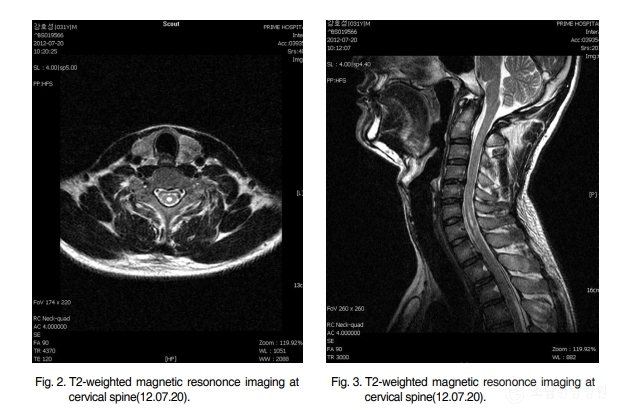

▲ 연구 대상은 33세 남성 환자로, 2012년 7월 무거운 물건을 들다가 발생한 목 통증과 양측 상지의 저림 증상이 발생했습니다. 경추부 MRI 검사 결과, C4/5 및 C5/6 경추 추간판 탈출증, 척수공동증, 후종인대골화증 등의 진단을 받았습니다.